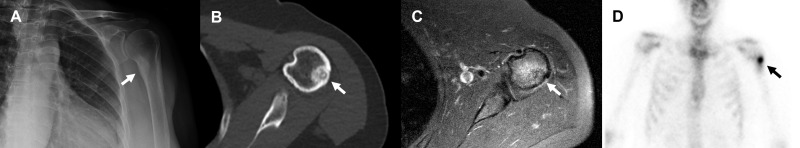

Introduction: Osteoid osteoma is a benign bone tumor that accounts for roughly 2-3% of primary bone tumors and up to 10-12% of benigns bone neoplasms. It is most commonly seen in young adults, and shows male predominance. Over the last years, minimally invasive thermal ablation techniques such as radiofrequency ablation have gained popularity over classical surgery. In this study we evaluate results and complications of CT guided osteoid osteoma radiofrequency ablation.

Materials and methods: In this retrospective cohort study all patients that were diagnosed with osteoid osteoma and treated using radiofrequency ablation between January 2014 and December 2022 were included. Pain was assessed using Visual Analog Scale (VAS) pre and post procedure. Technical success was established as positioning of the radiofrequency electrode in the nidus. Primary clinical success was defined as absence of pain after one radiofrequency session. All patients that required a second radiofrequency ablation were included in the overall clinical success group.

Results: During the studied period, 61 osteoid osteoma radiofrequency ablations were performed. Fiftyseven of them were included in this study, 32 were men and 25 female. Pre procedure median pain was 9 according to VAS score. Only 23 patients were treated as outpatient, the rest stayed in hospital for 24 hours. Median follow up time was 21,7 months (SD 8,3). Biopsy was performed in 52 patients. Technical success was accomplished in 57 patients (100%). Primary clinical success was 80,7% (46 patients). Those who continued with pain or had recurrence after a symptoms free period (11 patients), were treated with a second radiofrequency ablation, achieving an overall success rate of 94,7%. Only one patient suffered a minor complication (1,7%).